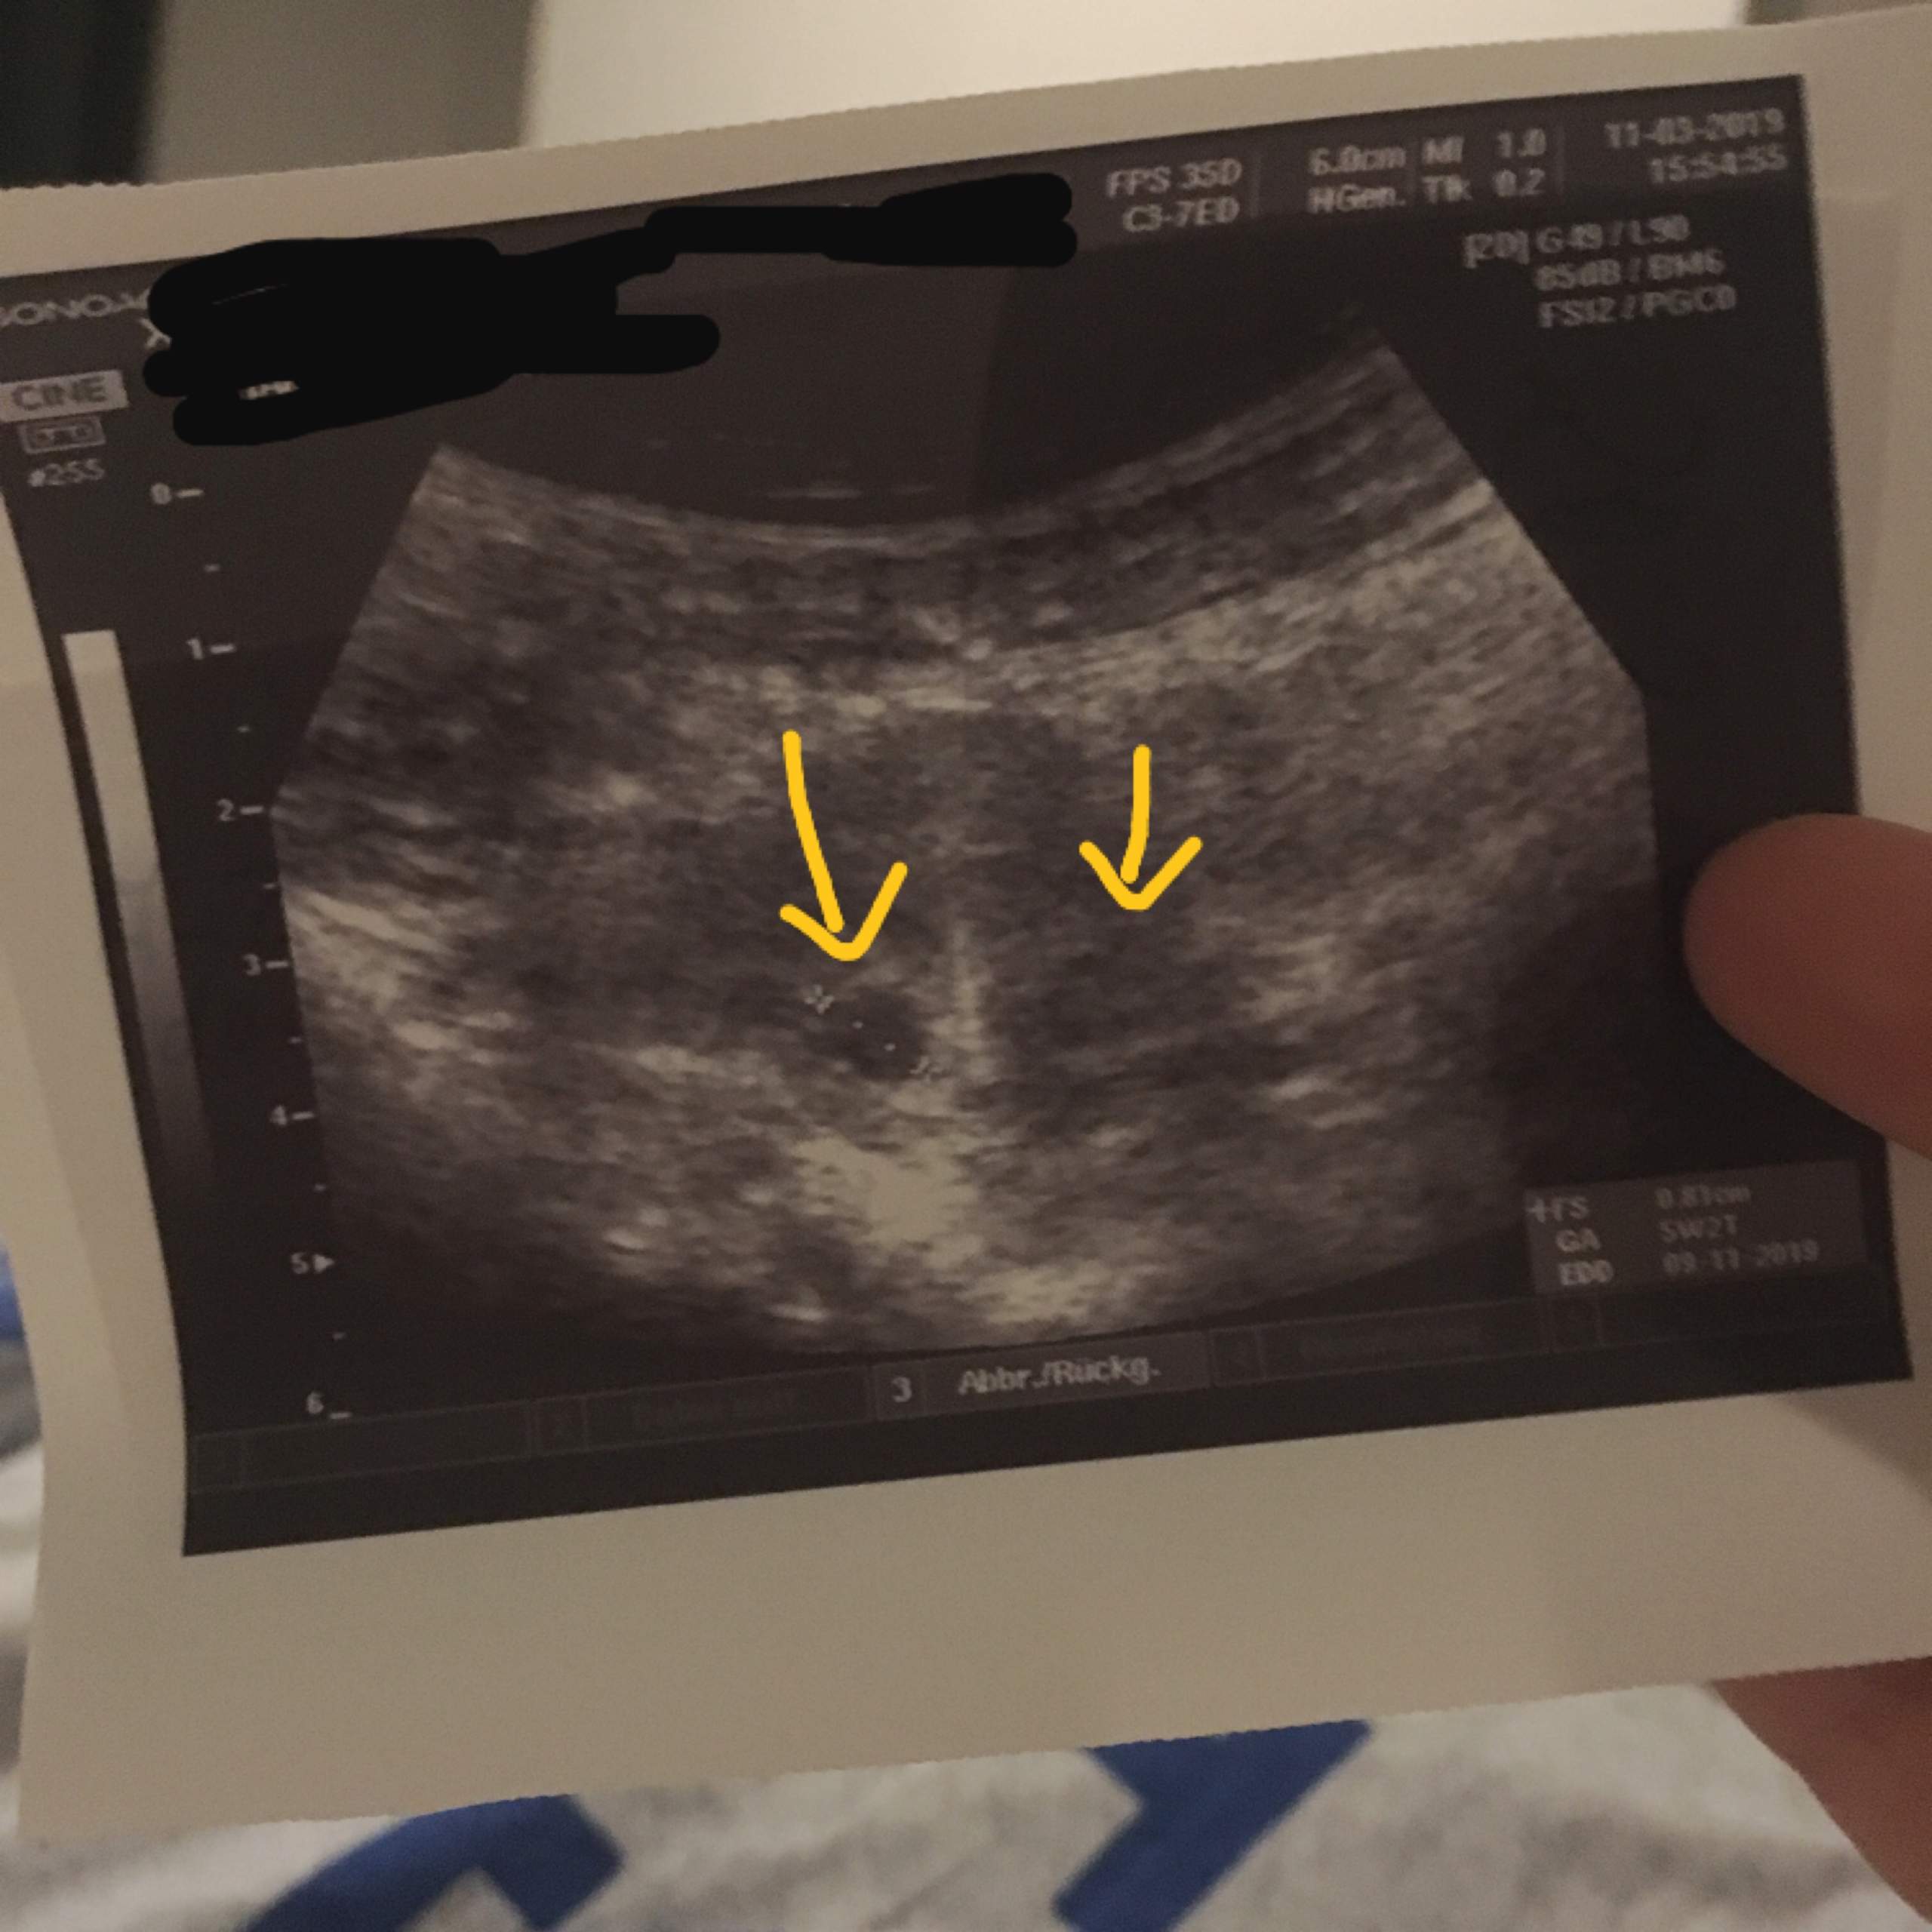

Meine FÄ meinet ich müsse abwarten aber 13 der Schwangerschaften scheffen die ersten 3 Monate nicht und nächste Woche soll ich wegen Weihnachten nochmal ins KH und Ultraschall machen lassen in der Hoffnung das man dann etwas. Nur Fruchthöhle und Dottersack in 7. 7 ssw ultraschall nur fruchthöhle 7 ssw.

Als ich in der 7 Woche war sah man die Fruchthöhle den Dottersack und den Embryo. Es kommt öfters vor dass um die 6SSW nur eine leere Fruchthöhle zu sehen ist. Sie vermuten eine Eileiterschwangerschaft.

Bei meiner tochter hat man bereits in der 61 ssw einen kleinen dottersack und ein embryo sehen können. Dottersack aber kein Embryo.